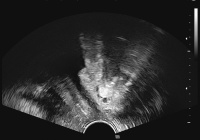

Kongressbericht: Belastungsinkontinenz - Individuell behandeln dank optimaler Diagnose. Aktuelle patientenspezifische Therapiekonzepte in der operativen Therapie der Belastungsinkontinenz. 14. und 15. Juni 2010, Wien

Journal für Urologie und Urogynäkologie 2010; 17 (3) (Ausgabe für Österreich): 51-53 Journal für Urologie und Urogynäkologie 2010; 17 (3) (Ausgabe für Schweiz): 50-52 Volltext (PDF) Abbildungen